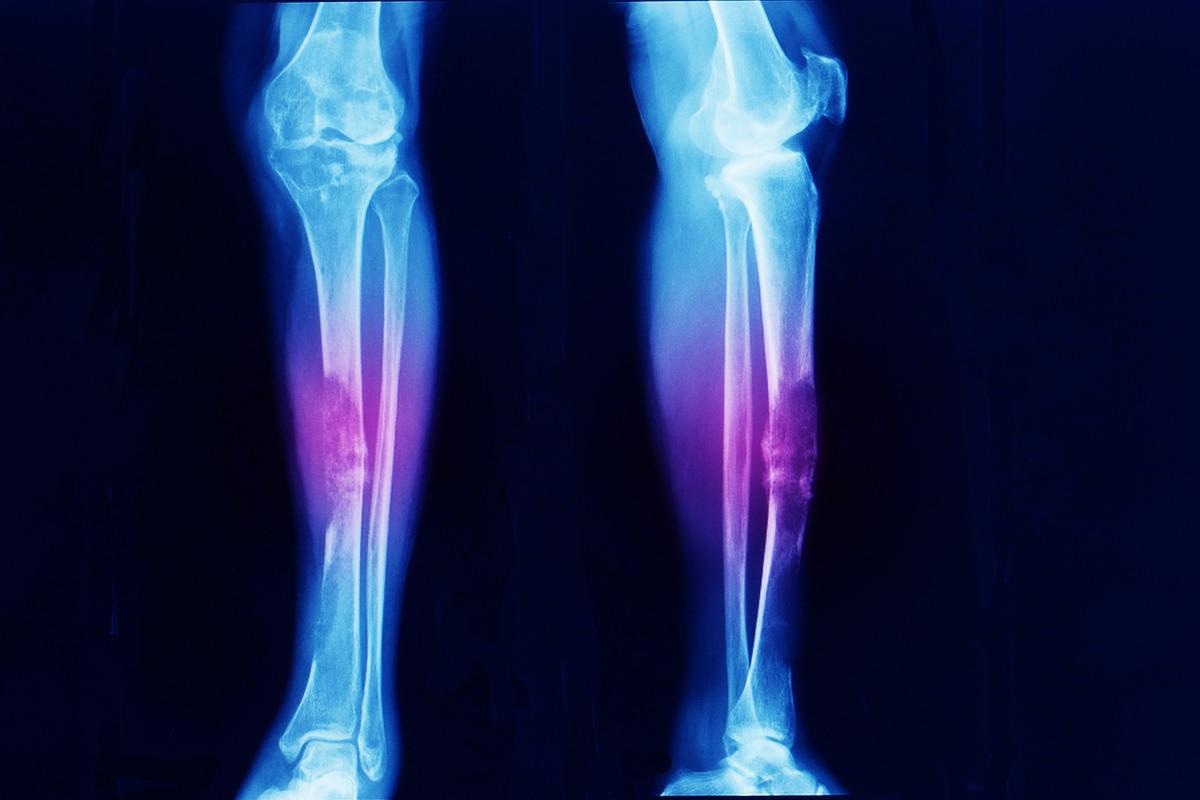

Local discomfort, bone swelling, and palpable bony masses are common clinical symptoms in the first decade of life and are frequently associated with bone malformation. Clinical findings include headache and cranial nerve palsy. Enchondromas on the extremities are frequently apparent as lumps implanted inside the phalanges, metacarpal, and metatarsal bones on physical examination. Long tubular bones, such as the tibia, femur, and/or fibula, are usually afflicted by enchondromas; flat bones, particularly the pelvis, can also be impacted. The lesions can affect numerous bones and are frequently asymmetrically distributed, affecting one side of the body solely or predominately. Bones that have been affected are frequently shorter and misshapen.

Clinical and conventional radiological examinations, rather than genetic testing, are used to diagnose Ollier disease. The most effective method for diagnosing numerous lesions and malignant transformation is radionuclide bone imaging. It can aid in the diagnosis and prognosis of Ollier disease. One of the most basic instruments for diagnosing bone illnesses is an X-ray. The lesions in Ollier disease are mostly oval and develop in the shaft and metaphysis of short or long bones.